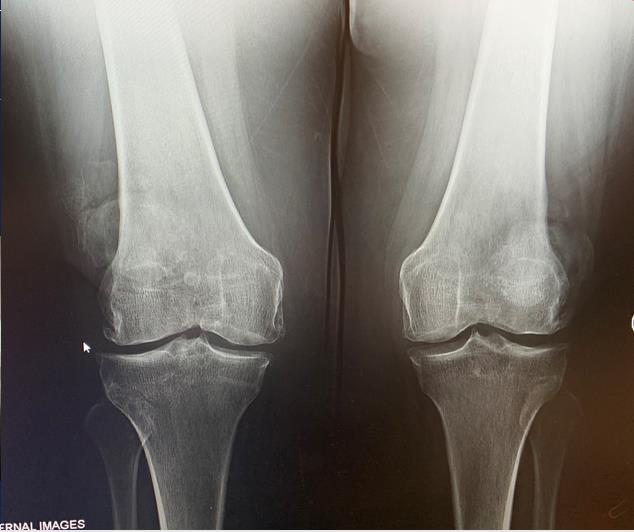

Knee Balancing Orthobullets . Measured resection is a total knee arthroplasty (tka) technique that relies on bony landmarks to set component placement and adapts the soft tissues to the chosen implant position. This article reviews different techniques to position tka implants, including kinematic alignment, which aims to restore the patient's. Soft tissue balancing during total knee arthroplasty (tka) is an important step for optimizing the outcome of the procedure and providing. Balance flexion and extension gaps by adjustment of polyethylene bearing thicknesss We compared knee arthroplasties performed using either a measured resection or gap balancing technique to determine if either operative.

Balance flexion and extension gaps by adjustment of polyethylene bearing thicknesss Soft tissue balancing during total knee arthroplasty (tka) is an important step for optimizing the outcome of the procedure and providing. This article reviews different techniques to position tka implants, including kinematic alignment, which aims to restore the patient's. We compared knee arthroplasties performed using either a measured resection or gap balancing technique to determine if either operative. Measured resection is a total knee arthroplasty (tka) technique that relies on bony landmarks to set component placement and adapts the soft tissues to the chosen implant position.